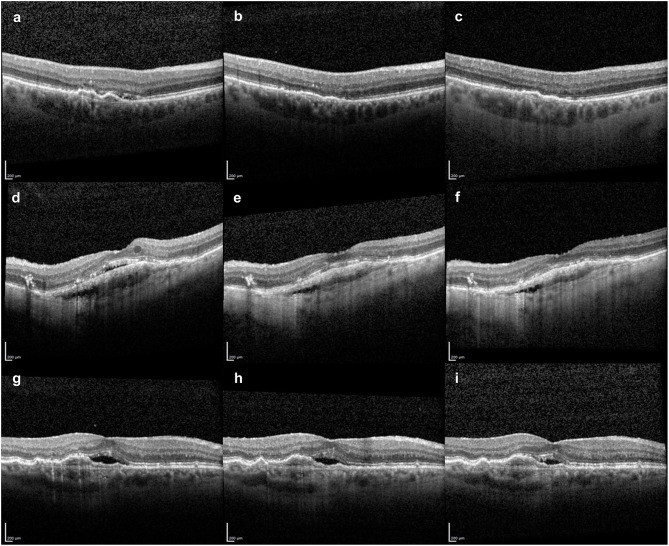

Results: The mean treatment-interval before the fifth injection with Faricimab was 5.35 ± 1.49 weeks and was therefore significantly longer compared to the monthly interval with Aflibercept (p < 0.001). Mean baseline central retinal thickness (CRT) was 267.82 ± 76.00 µm and decreased significantly already at month 1 to 249.61 ± 65.35 µm (p < 0.001). After the fourth intravitreal injection, there was no significant change with a CRT of 252.95 ± 56.96 µm (p = 0.134). There was a significant reduction in the number of patients showing subretinal fluid (SRF) and intraretinal fluid (IRF). In eyes with fibrovascular pigment epithelium detachment (PED), an interval extension was not possible in more than half of the cases. Eyes with serous and drusenoid PED and a rather high amount of hyper-reflective foci (HRF), the majority showed a significant response after the switch.

Conclusion: An initial loading dose could be beneficial to elongate Faricimab's additional effect of reducing retinal swelling in eyes with nAMD and previous low-response to Aflibercept. Serous and drusenoid PEDs seem to benefit more than fibrovascular PEDs. A high amount of intraretinal HRF in patients with PED was a sign for good respondence to Faricimab.